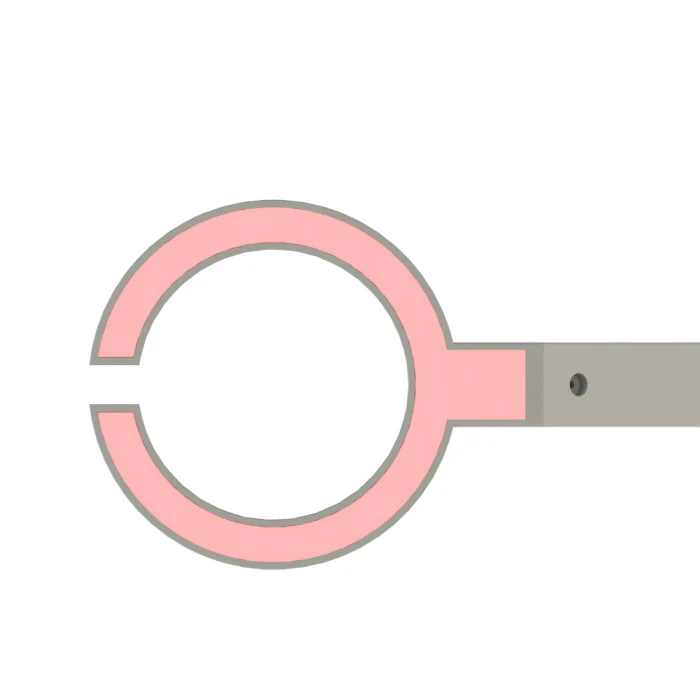

Взрослая детская визуализация инфракрасный васкулярный IV вены Finder Transilluminator вены просмотра TN88

Наше портативное устройство для просмотра Вены-Доступный портативный обнаружитель вен для общего доступа вены у взрослых и детей.

Питание от зарядного устройства непосредственно при использовании с 15 светодиодами, управляемыми одним переключателем.

Он используется для эффективного доступа IV в аварийной медицине.

Глубина обнаружения: <10 мм

Минимальное Обнаружение Вены: 0,1 мм

Адаптер питания: 110 V-220 V 50-60Hz